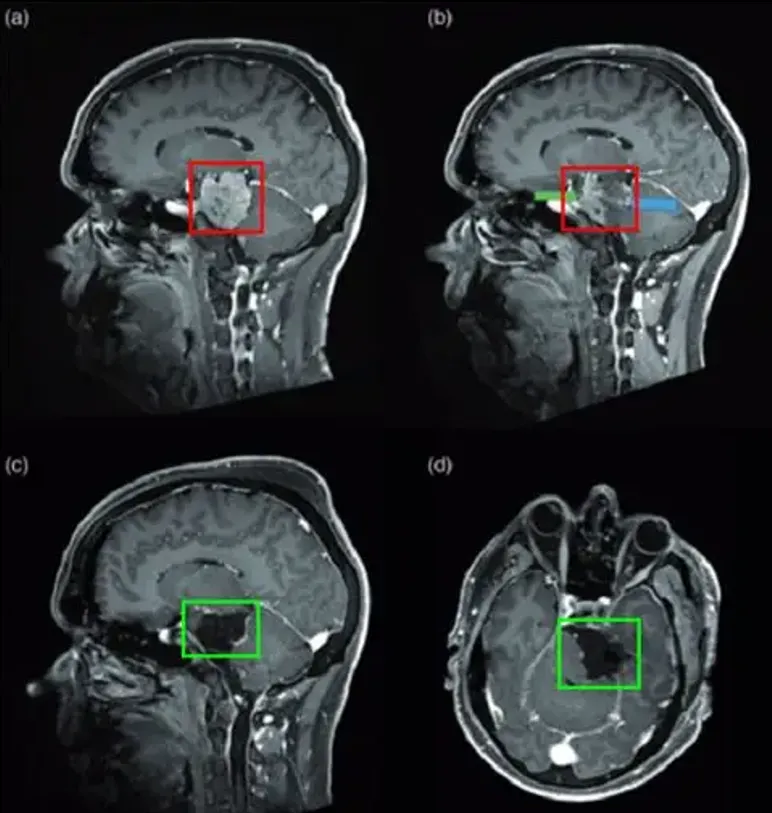

图(a)为术前脑膜瘤影像图

图(b)为血管栓塞后肿瘤位置

图(c)、图(d)显示肿瘤已被完全切除

颞部开颅术和前岩部切除术。脑膜瘤在肿瘤切除的不同阶段交替进行超声抽吸和周围结构的仔细解剖,从血管的角度观察,硬脑膜边缘被切断以完成肿瘤的断流。最终手术切除是完全的(辛普森I级切除),周围的颅神经IV、V、VII、VIII等均保存完好,患者术后神经功能完好。